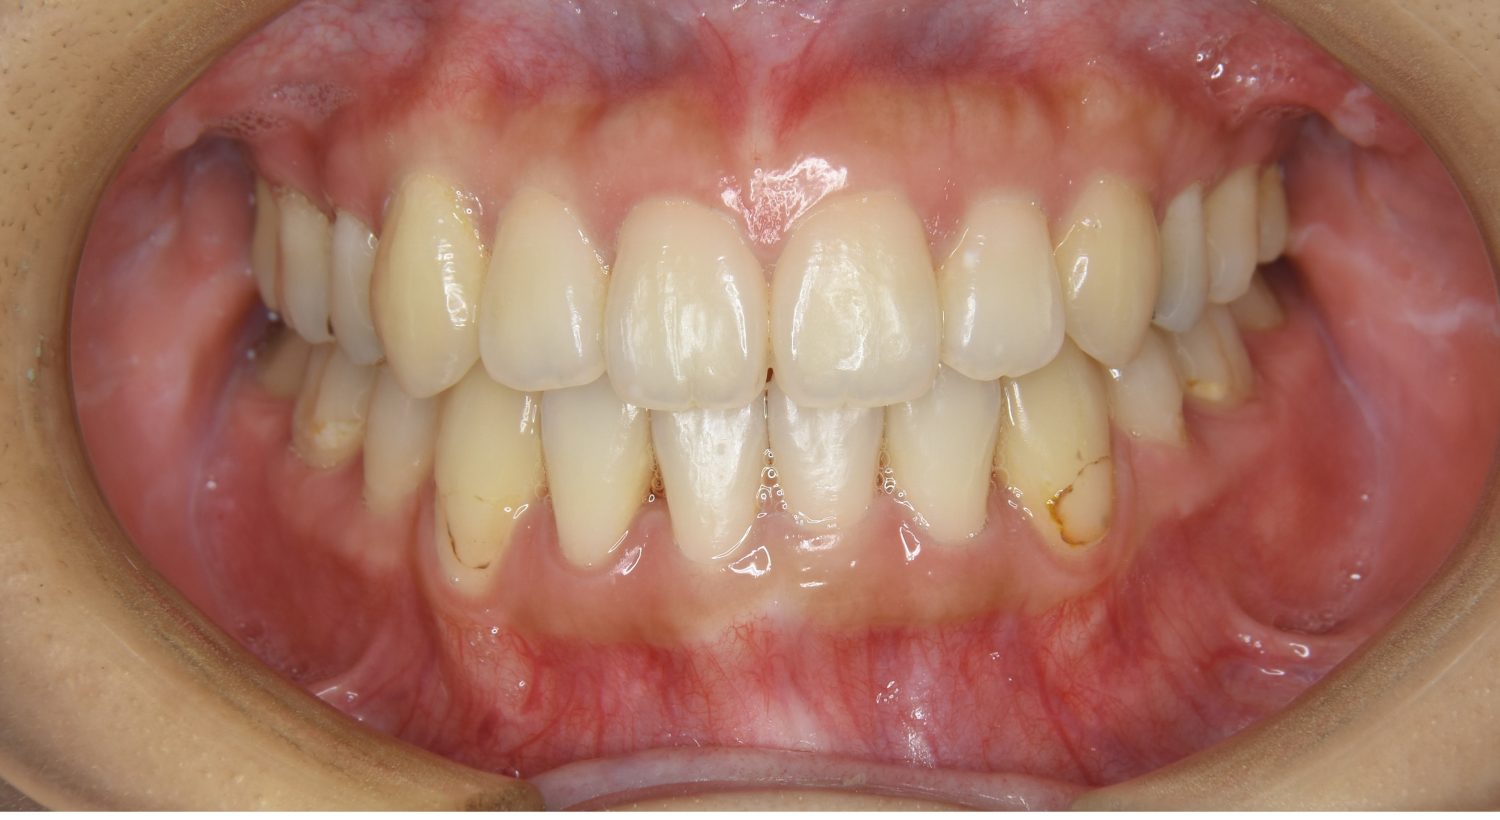

前歯部開咬の症例紹介②

Before

After

主訴

前歯で物が噛めない

治療内容

上下ラビアルブラケット(唇側装置)に矯正用アンカースクリューを併用し非抜歯で治療を行いました。

治療費

1,000,000 円(税込)

治療期間

26ヶ月

通院回数

27回

想定されたリスク

※歯根吸収、歯肉退縮、歯髄壊死、顎関節症状

丸山和宏先生

ピーススマイル矯正歯科

上下の前歯が開いており前歯では全く噛めていない状態でした。臼歯の圧下を行うことで機能面のみでなく審美面も改善しました。